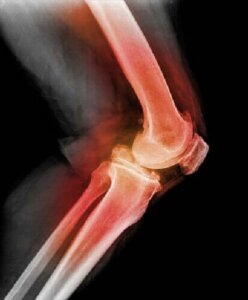

Aby zdiagnozować zwichnięcie rzepki lub stawu kolanowego, lekarz najpierw przeprowadzi badanie organoleptyczne i zegnie Twoje kolano, wyginając je w różnych kierunkach. Używając promieni rentgenowskich, obrazowania metodą rezonansu magnetycznego (MRI) lub tomografii komputerowej (CT), może zobaczyć obrazy zwichniętej rzepki i innych urazów kolana.